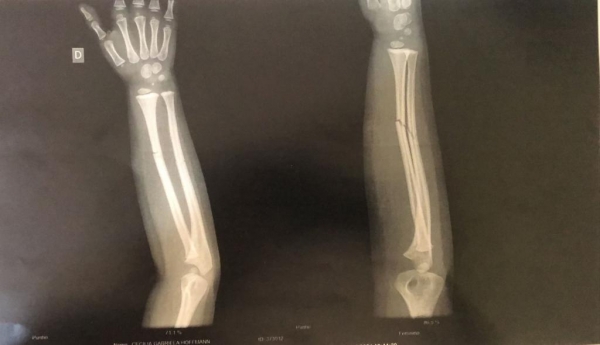

O resultado do exame (imagem acima) apresentou duas fraturas fechadas no braço da criança, que voltou para o hospital Bom Pastor após fazer o Raio-X, e ficou aguardando em um leito a transferência para algum hospital da região a fim de receber atendimento especializado.